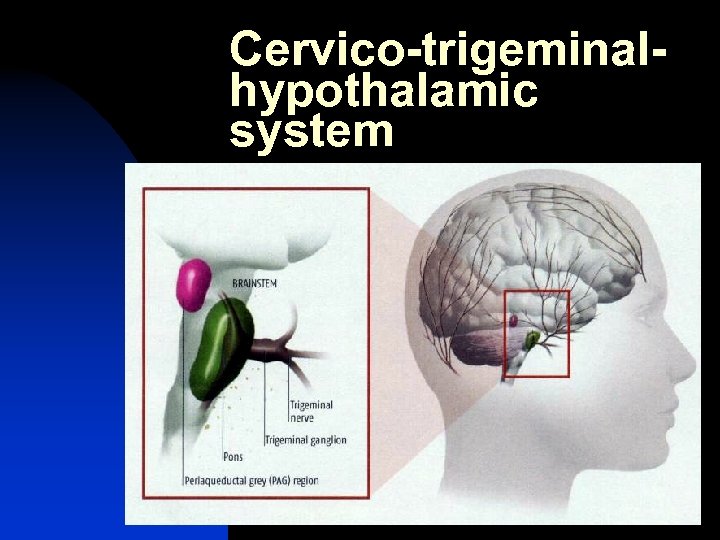

Cervico-trigeminalhypothalamic system

Cervico-trigeminalhypothalamic system